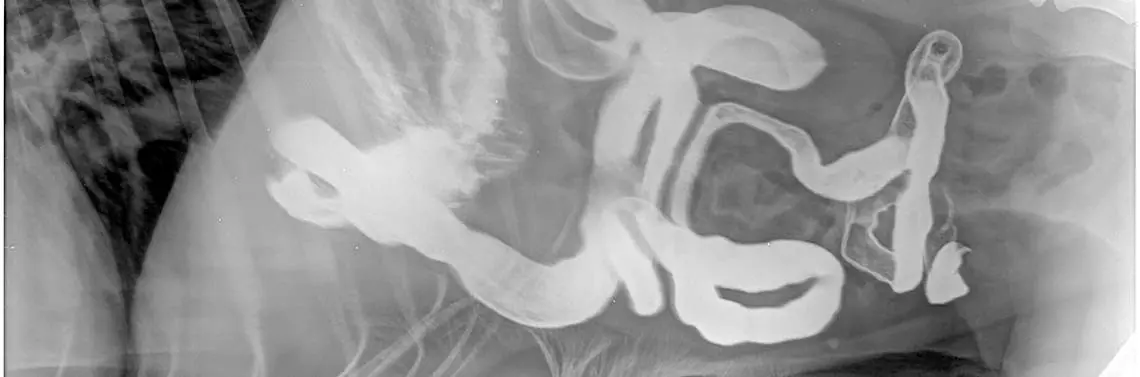

Z tego powodu wszelkie zmiany, które znajdują się w świetle przewodu pokarmowego lub w ścianie przeciwległej do wysyłanych przez sondę ultradźwięków, nie mogą być uwidocznione. Lekarz weterynarii dla uzupełnienia diagnostyki posługuje się obrazem rentgenowskim, czyli tzw. diagnostyką cieni. Do powstawania obrazu RTG dochodzi poprzez pochłanianie promieni X przez tkanki. Ze względu na podobną gęstość radiologiczną wielu narządów jamy brzusznej, odczytanie tych cieni jest niezwykle trudne i często wymaga wykonania wielu projekcji. Nierzadko lekarz prowadzący decyduje o tzw. badaniu kontrastowym przewodu pokarmowego (fot. 13A–B), aby upewnić się, że jego drożność i praca są prawidłowe.

Badanie kontrastowe pozwala wykluczyć obecność ciała obcego, które nie powoduje całkowitej niedrożności i nie jest dobrze widoczne w obrazie rentgenowskim [dobrze widoczne są wszelkiego rodzaju kamienie czy metalowe części oraz charakterystyczne kształty nie przypominające prawidłowych narządów – (fot. 10–11)]. Rentgen jamy brzusznej z podaniem doustnym środka kontrastującego pozwala ocenić, czy nie doszło do uszkodzenia ściany [22].

W przypadku podejrzenia uszkodzenia ściany lekarz badający może zdecydować o podaniu doustnym jałowego środka kontrastującego (podawanego zwykle dożylnie), aby można było bezpiecznie wykonać zabieg otwarcia jamy brzusznej. Pełne badanie kontrastowe przewodu pokarmowego wymaga regularnego wykonywania zdjęć w określonych odstępach czasu – dlatego jeśli obraz rentgenowski nie jest jednoznaczny, jego zakończenie wymaga wykonania ostatniej projekcji nawet po 24–48 godzinach od jego rozpoczęcia. Czas badania i szczególne uwzględnienie odcinka badania ustala lekarz, dlatego liczba projekcji i czas badania mogą być różne.

Fot. 13A

Fot. 13B

Badanie kontrastowe przewodu pokarmowego psa z ciężkim zapaleniem dwunastnicy. Na zdjęciach widoczne poszerzenie pętli jelita w lokalizacji dwunastnicy potwierdzone badaniem ultrasonograficznym. Kontrast na zdjęciu jest praktycznie „biały”, a jego płynny lub papkowaty charakter pozwala na prześledzenie pracy poszczególnych odcinków przewodu pokarmowego. Badanie kontrastowe jest długie, ale bardzo pomocne w podjęciu decyzji o laparotomii diagnostycznej: A) projekcja boczna, B) projekcja grzbietowo-brzuszna. (Zdjęcia dzięki uprzejmości lek. wet. Anny Jastrzębskiej, Przychodnia weterynaryjna „Amicus” Zielona Góra)